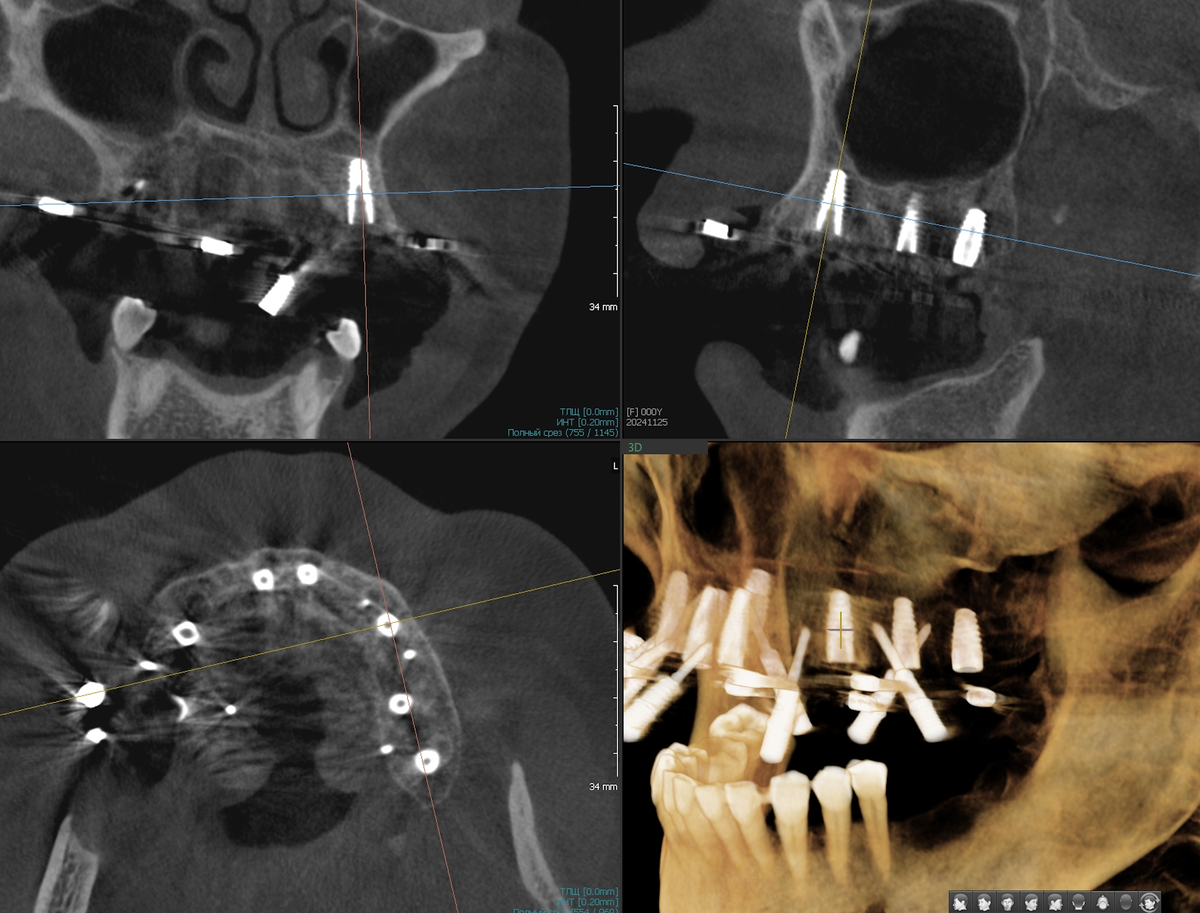

КТ-планирование

Компьютерная томография - в зону исследования должны входить пазухи и суставы (ВНЧС) полностью. Хирург видит кость в 3D формате. Каждый миллиметр, каждую особенность, каждую важную заковырку.

Затем, в специальной программе соединяются КТ, сканы и зубы (протез), которые спроектировал техник. Под это дело виртуально расставляем имплантаты. Подбираем углы, глубину, диаметр. Проверяем расстояние до важных структур.